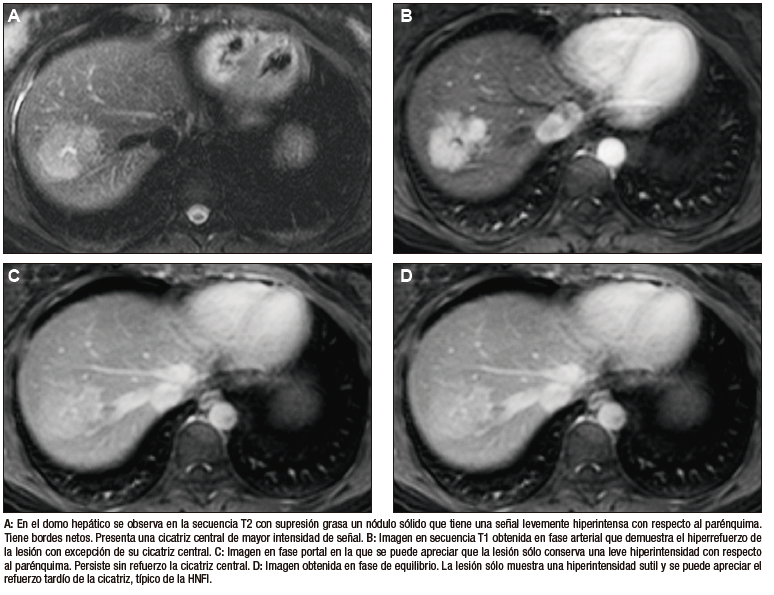

La HNF se manifiesta como uno o más nódulos (múltiple en aproximadamente 20%) de bordes netos y contornos lobulados. En la TCMC tiene densidad similar o apenas menor a la del parénquima adyacente. Si la cicatriz es visible (60%) en la TC es hipodensa. (Figura 3) En la RM su señal es isointensa o apenas hipo o hiperintensa en T1 e isointensa o un tanto hiperintensa en T2. (Figura 4) La cicatriz es hiperintensa en T2 (visible 80% en la RM), característica clave para diferenciarla del hepatocarcinoma fibrolamelar (cuya cicatriz es hipointensa en T2 por fibrosis o por calcificación). Por otra parte, en algunos casos la diferenciación puede ser difícil ya que ambas son lesiones que ocurren en pacientes jóvenes con hígado sano y presentan similar aspecto y comportamiento poscontraste. Típicamente, la lesión realza intensamente en la fase arterial en forma homogénea y su densidad (o intensidad de señal en la RM) disminuye en fases sucesivas pero suele persistir levemente reforzada con respecto al hígado.4, 5 Los hepatocitos que forman la HNF son positivos para las proteínas transportadoras, característica que, sumada a la presencia de conductos biliares, explican el refuerzo de estas lesiones en la fase hepatobiliar en la RM con empleo de contraste hepatoespecífico. Esto permite establecer el diagnostico con un alto grado de certeza y alejar (sin descartar absolutamente) la posibilidad de un adenoma hepatocelular. El refuerzo puede ser isointenso con el parénquima, difusamente hiperintenso e hiperintenso en la periferia. (Figura 5) Dada la naturaleza benigna de la lesión, carece de riesgo de malignidad y el manejo de la HNF es conservador.8 Si el diagnóstico por imágenes es firme, no se requiere seguimiento. Si la lesión es sintomática, presenta características no típicas, es pediculada o exofítica, el caso debería ser sometido a discusión por un equipo multidisciplinario. La indicación de cirugía por la HNF es excepcional en casos sintomáticos o en raras circunstancias como sangrado o rotura.

Figura 4. HNF en la RM